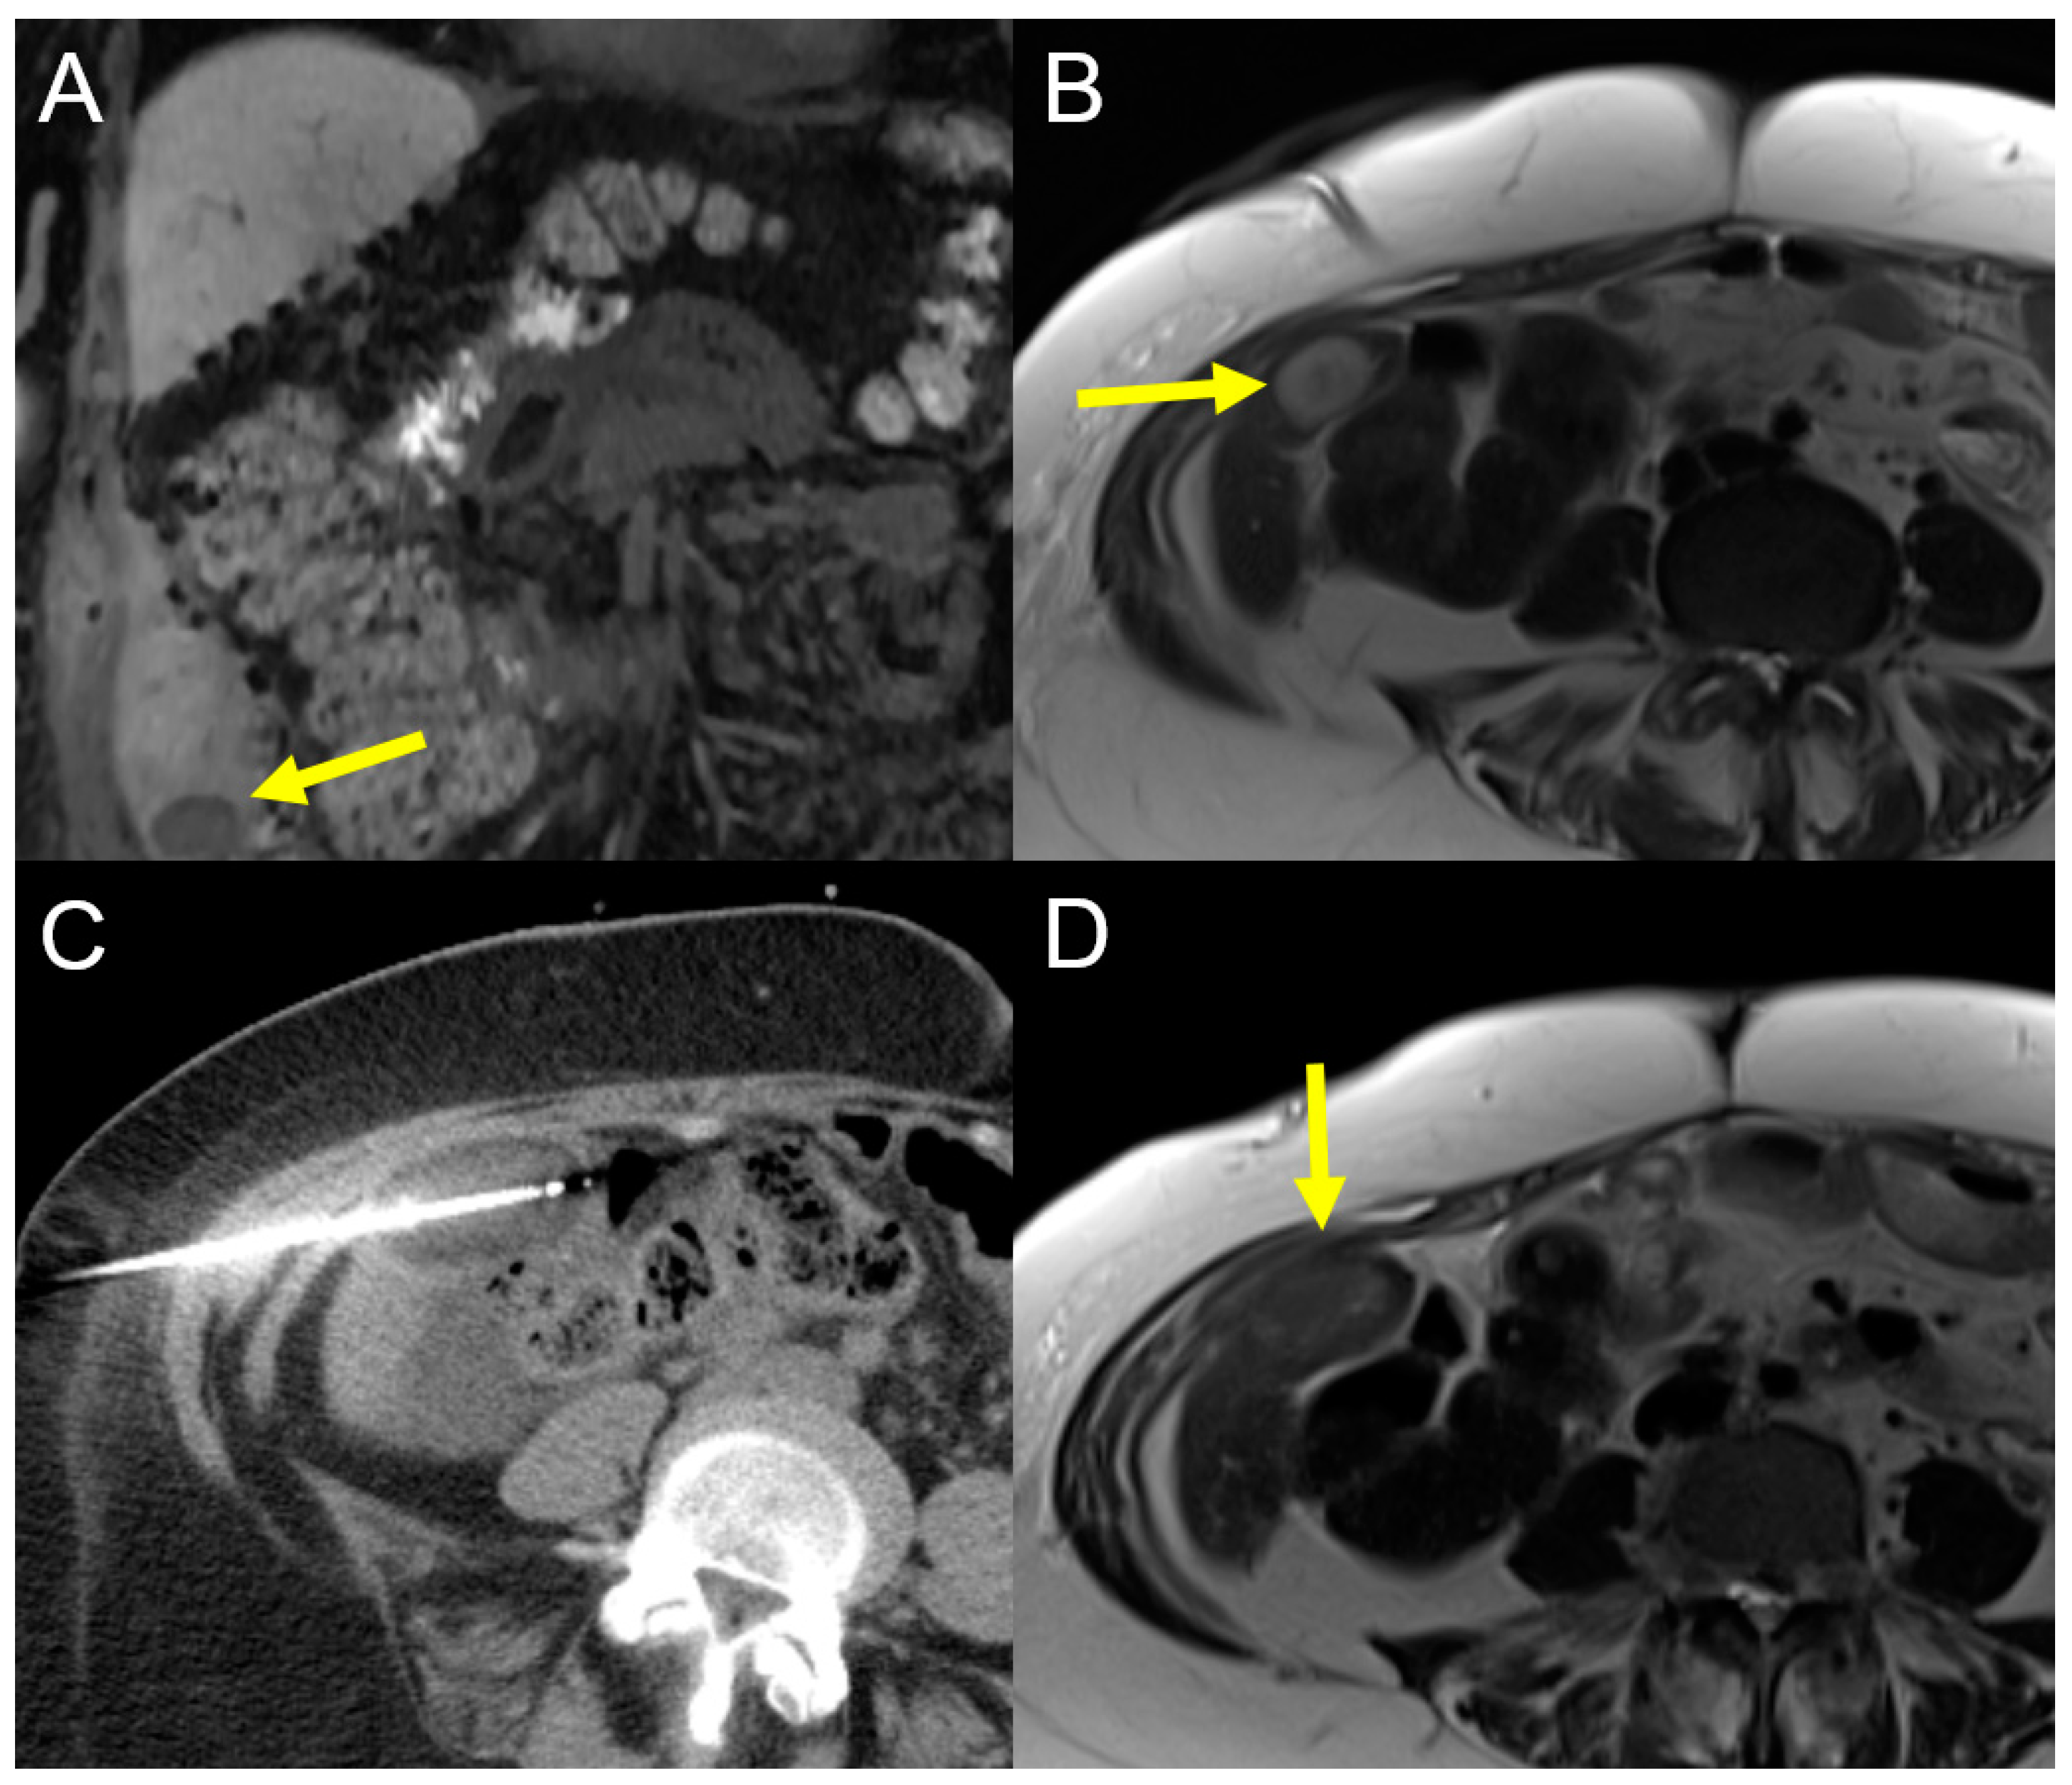

2.2.1. Computed Tomography High-Dose-Rate Brachytherapy (CT-HDRBT)

- Schnapauff, D.; Denecke, T.; Grieser, C.; Collettini, F.; Seehofer, D.; Sinn, M.; Banzer, J.; Lopez-Hanninen, E.; Hamm, B.; Wust, P.; et al. Computed tomography-guided interstitial HDR brachytherapy (CT-HDRBT) of the liver in patients with irresectable intrahepatic cholangiocarcinoma. Cardiovasc. Intervent Radiol. 2012, 35, 581–587. [Google Scholar] [CrossRef]

- Kamphues, C.; Seehofer, D.; Collettini, F.; Bahra, M.; Neuhaus, P.; Wust, P.; Denecke, T.; Gebauer, B.; Schnapauff, D. Preliminary experience with CT-guided high-dose rate brachytherapy as an alternative treatment for hepatic recurrence of cholangiocarcinoma. HPB 2012, 14, 791–797. [Google Scholar] [CrossRef]

- Jonczyk, M.; Collettini, F.; Schnapauff, D.; Geisel, D.; Boning, G.; Feldhaus, F.; Denecke, T.; Wieners, G.; Hamm, B.; Gebauer, B. Cholangiocarcinoma: CT-guided High-Dose Rate Brachytherapy (CT-HDRBT) for Limited (<4 cm) and Large (>4 cm) Tumors. Anticancer Res. 2018, 38, 5843–5852. [Google Scholar] [CrossRef] [PubMed]